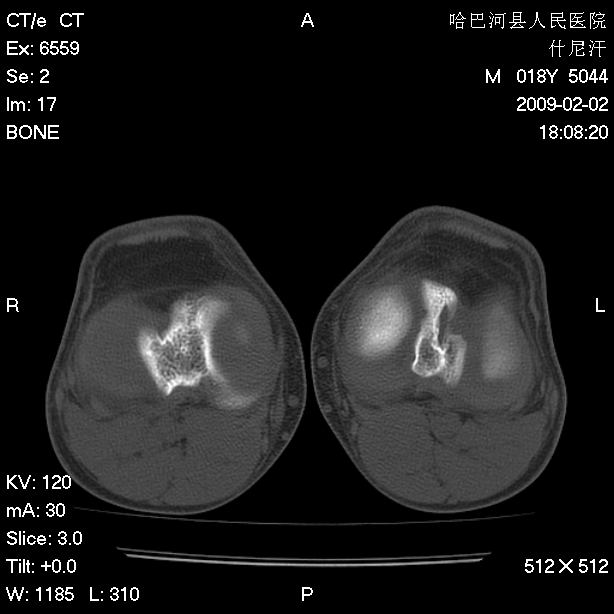

标题: CT17889:外伤后右膝关节反复疼痛3年余 [打印本页]

标题: CT17889:外伤后右膝关节反复疼痛3年余

ct未见明显异常。关节腔未见明显积液,半月板未见明显撕裂。但最好还是mri看看韧带及半月板情况。